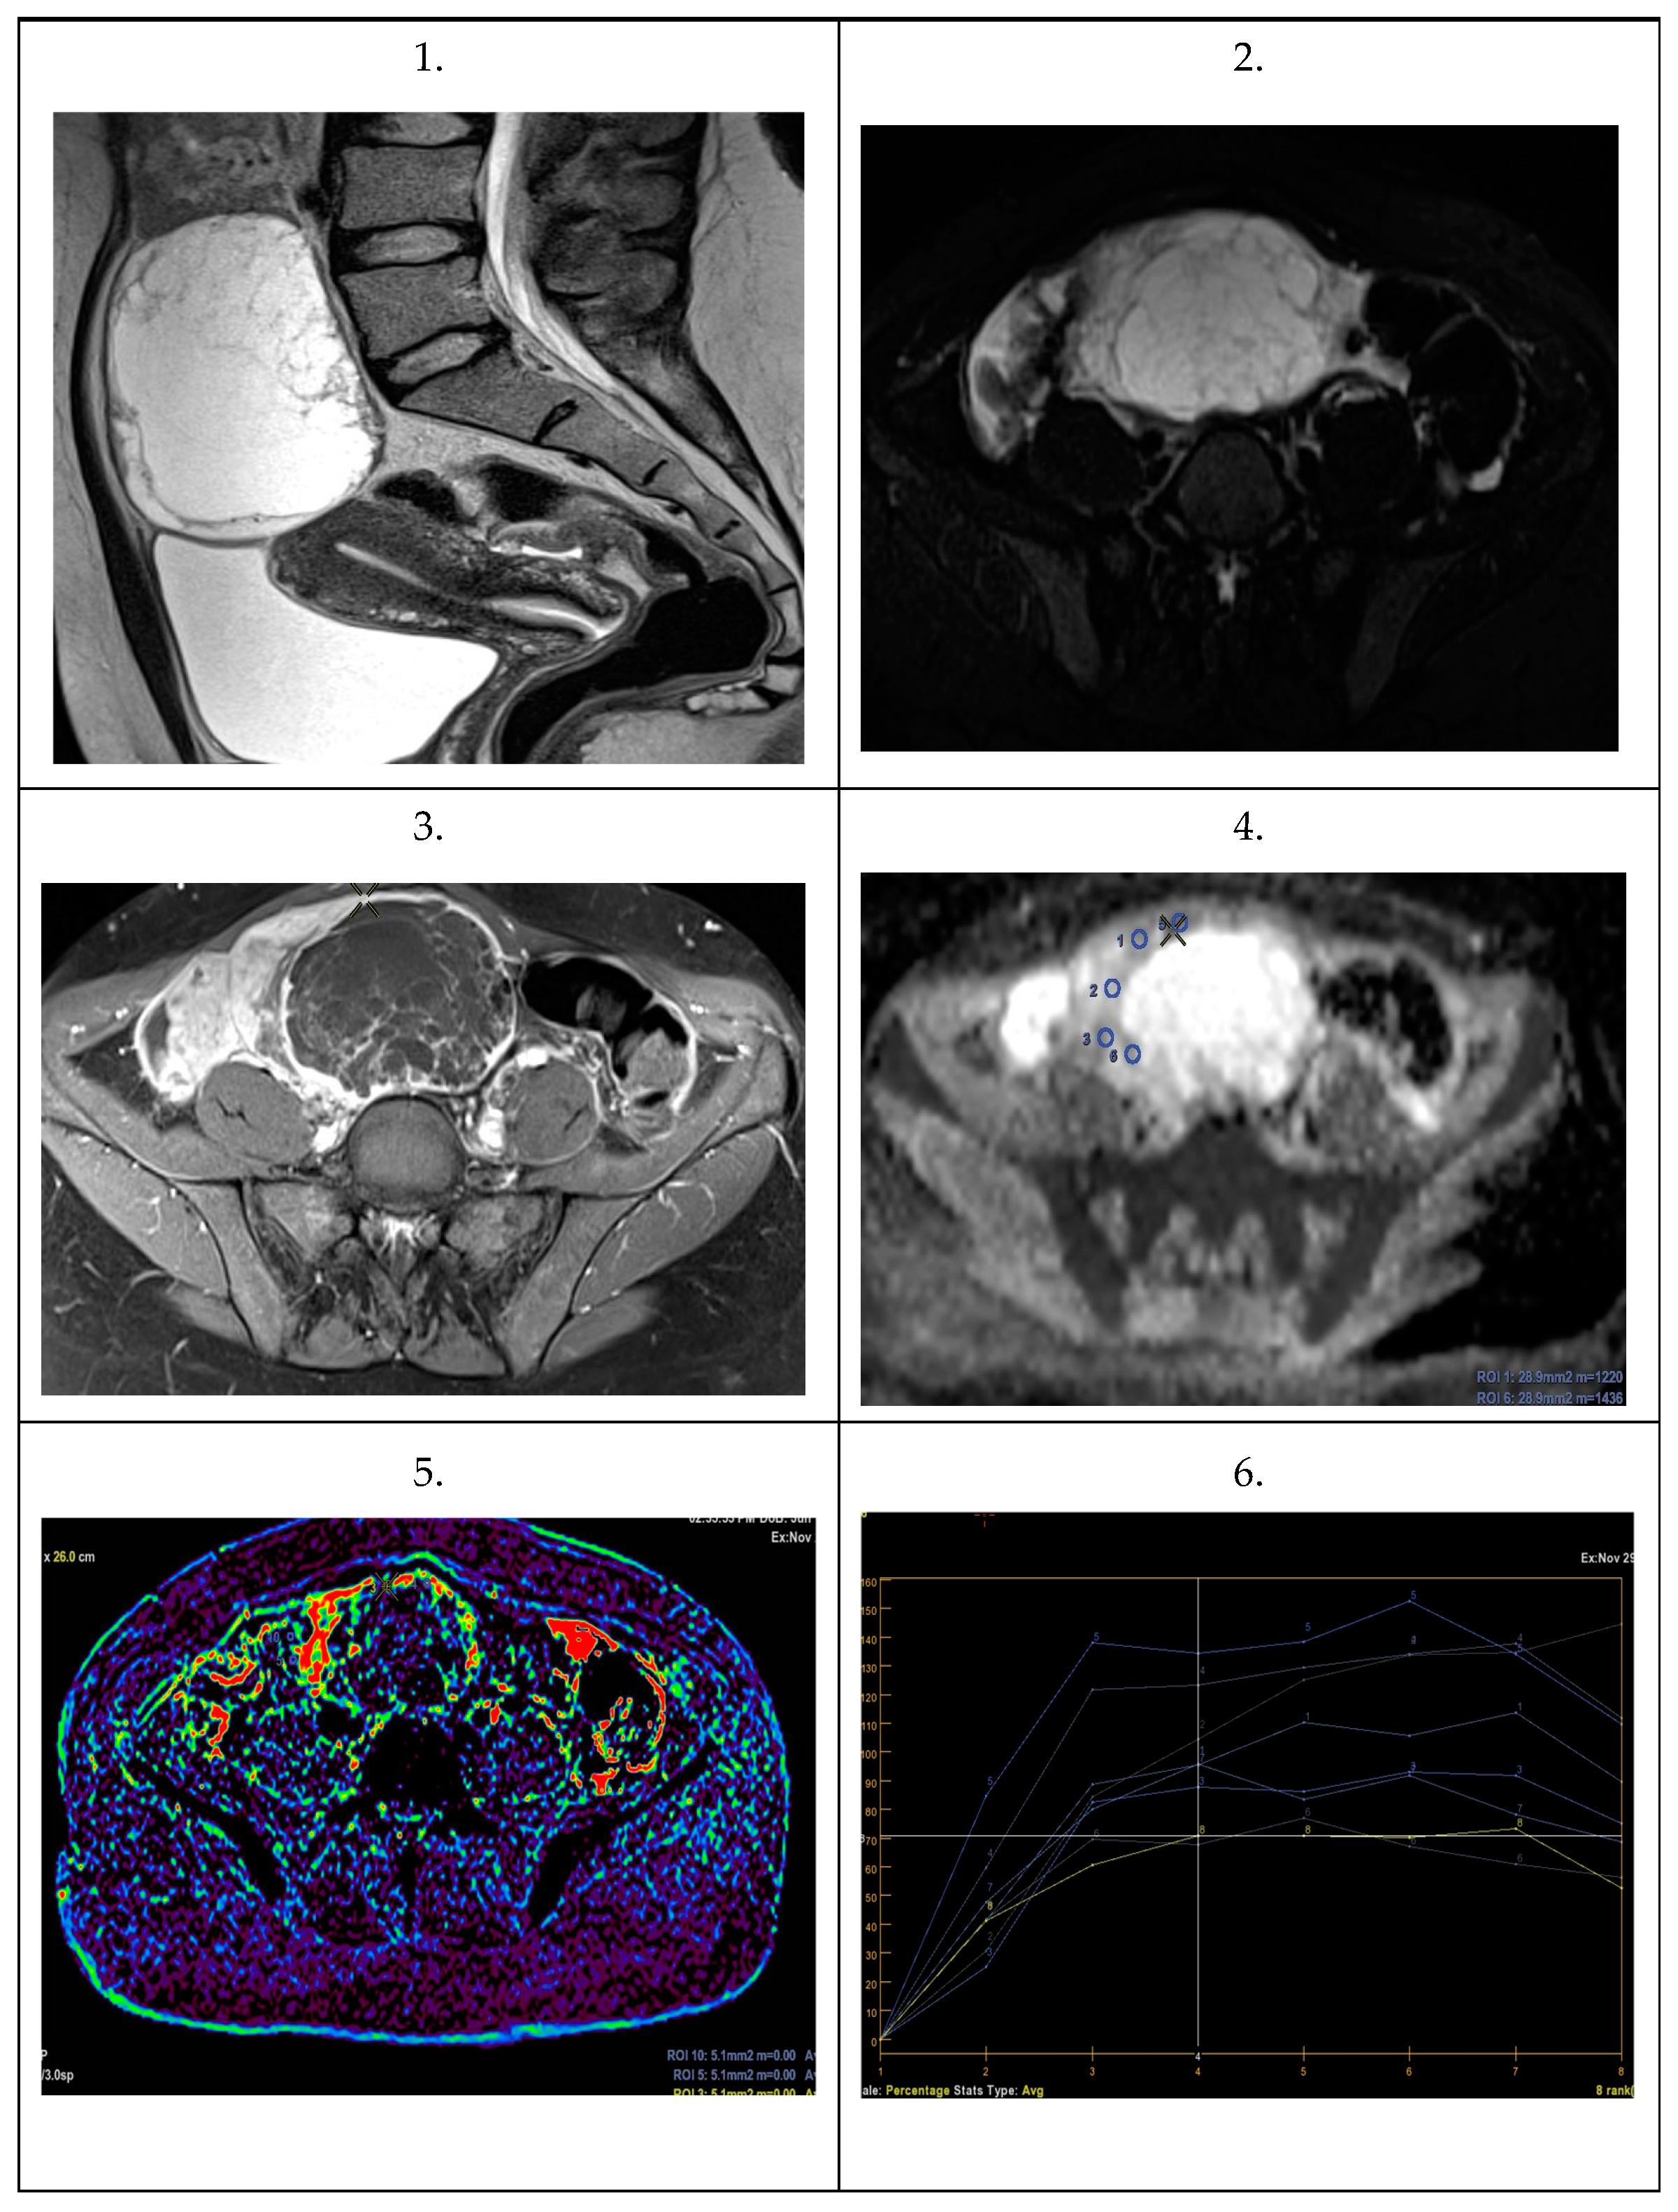

| Parameter | Statistic | Total | Primary Ovarian Cancer | Metastatic Ovarian Tumor | p Value |

|---|---|---|---|---|---|

| N = 57 | N = 10 | N = 47 | |||

| ADC 1 | Median | 851 | 1465.5 | 842 | 0.0001 |

| Q1–Q3 | 814–888 | 1430.5–1537.25 | 810.5–875 | ||

| ADC 2 | Median | 843 | 1434 | 821 | 0.0001 |

| Q1–Q3 | 800–890 | 1345.75–1643 | 800–872 | ||

| ADC 3 | Median | 846 | 1631.75 | 824 | 0.0001 |

| Q1–Q3 | 808–899 | 1400.5–1678.25 | 806–871.5 | ||

| ADC 4 | Median | 865 | 1442 | 845 | 0.0002 |

| Q1–Q3 | 811–998 | 1230.25–1627.35 | 809–895 |

| TTP | Median | 157 | 410 | 154 | 0.0001 |

| Q1–Q3 | 149–171 | 370–465 | 147.5–161 | ||

| Perf.Max En. | Median | 167 | 141 | 167 | 0.5 |

| Q1–Q3 | 143–193 | 135.25–198.25 | 145–189.5 |